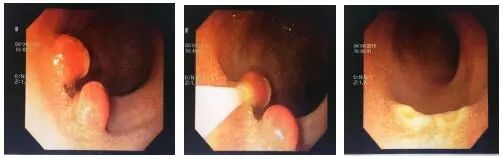

家长回忆说:患儿4月龄时家长曾发现患儿“小屁屁”有一个蚕豆大小的肉团脱出,大便时还伴有少量血液。由于这肉团不痛不痒,排便后很快还纳,未引起家长的重视。随后又发现了便血,由于量很少,亦没有引起家长的足够重视。此次就诊主要是家长发现有所长大的“小肉团”再次脱出,需用手帮助还纳,而且排便时出血量增多。小儿消化内科的内镜团队及麻醉科医师共同会诊后为患儿制定了无痛内镜下检查及同时行微创手术的“一次诊疗”方案,以便减轻患儿痛苦,达到有效切除息肉的目的。目前患儿恢复情况良好,无并发症发生。

关于肠息肉,李春伟谈到:日常生活中家长要特别注意两大症状:一是便血、二是肉团。肠息肉多为间断性、无痛性少量便血,血附于大便表面,血色鲜红,个别患儿可因息肉自行脱落而大量便血,少数患儿因长期便血而出现贫血。低位息肉随大便脱出于肛门口时易被发现,多为圆形、表面鲜红色的“小肉团”,大部分有蒂,用手轻轻推送可还纳入肛门内。个别患儿亦可发生息肉蒂扭转、崁顿坏死。部分高位的大息肉可因肠蠕动受阻或蒂柄牵引肠壁,而引起腹痛甚至肠套叠。多数高位息肉则难以被发现,需要借助超声或结肠镜检查。